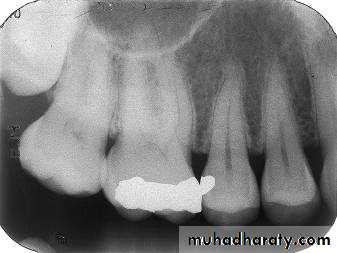

Premolar bitewing. A, Film placement. B, Resultant radiograph.

AB